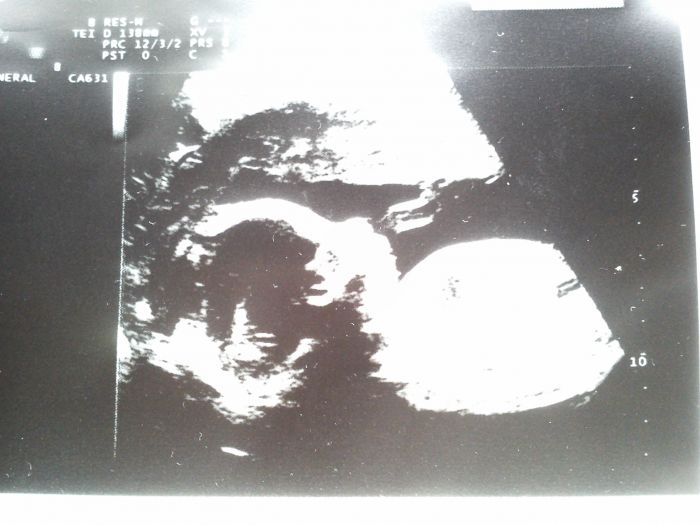

Ahoj holky, tak mi jdeme na velký UTZ příští týden a dozvíme se i výsledky z plodové vody. Konečně jsem Vás dočetla a když čtu, že někoho UTZ bolel, tak to musí být hrůza. Já to neznám, vždy to bylo fajn. Mě někdo asi mačkat břicho, tak se budu bát. V noci manžel teď chodí spát i do obýváku, protože se vrtí a bojí se, aby nás nebouchnul, když už se nám to povedlo mít toho prcka :). Jsem ráda, že jste většinou v pořádku a všem gratuluji k těm prdelkám. Náš Tomášek má teď 260 g a přez den je moc hodnej a chvilku o něm vím večer :). Přeji všem, aby výsledky byly v pořádku a dejte info. Vkládám foto našeho spícího Tomáška :).

Pekne si hovi Tomasek :-) Me tak mrzi,ze mi dr zapo vytisknout tu fotku. Na monitoru mi ukazal jen nohu a pak jsme se bavili o tom tvrdym brichu a zamluvilo se to. Takze jsem poradne nic nevidela. No ten tyden jeste musim vydrzet:-))) Pak si vezmem priklad z Misule s budem vkladat,ok? Ted to tu bude plne krasnych tvaricek:-) A doufam i krasnych pocitu z utz! No a me uz cele odpo paradne pali zaha. Dnes je nejaky den nadelenicek- nejdriv ty prvni krece v litku a ted ta zaha :-))) Jenze ja se pred chvili kochala ve sprse brichem a tak me nemuze nic tak banalniho pokazit slastny pocit :-)